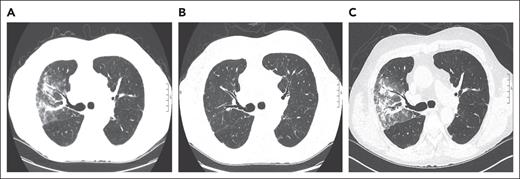

A 73-year-old man with a history of myelodysplastic syndrome, who received a nonmyeloablative allogeneic peripheral blood stem cell transplant (PBSCT), presented with progressive dyspnea, a nonproductive cough, and hypoxemia a year after HCT. Weeks before presentation, the patient was newly diagnosed with cGVHD of the skin. A chest computed tomography (CT) scan showed upper lobe predominant ground-glass opacities in a subpleural and peribronchovascular distribution (Figure 1A). The patient was treated for infectious pneumonia with levofloxacin without improvement. Clinical history did not reveal an antecedent exposure to medications associated with OP. Bronchoscopy with bronchoalveolar lavage (BAL) was performed, and microbiology culture results for bacterial, fungal, and viral pathogens were negative. On the basis of a lack of association with known pulmonary toxic medications or infectious agents, HCT-OP was diagnosed, and prednisone (1 mg/kg per day) was initiated with a slow taper over 4 months. The patient’s clinical symptoms rapidly resolved, including his skin cGVHD, and radiological improvement was achieved (Figure 1B).

Representative coronal images from a noncontrast chest CT scan. (A) CT scan of the chest, demonstrating a right-sided upper lobe–predominant, peripheral ground-glass opacity at the diagnosis of organizing pneumonia. (B) CT images after 4 months of treatment with prednisone, demonstrating resolution of opacities.